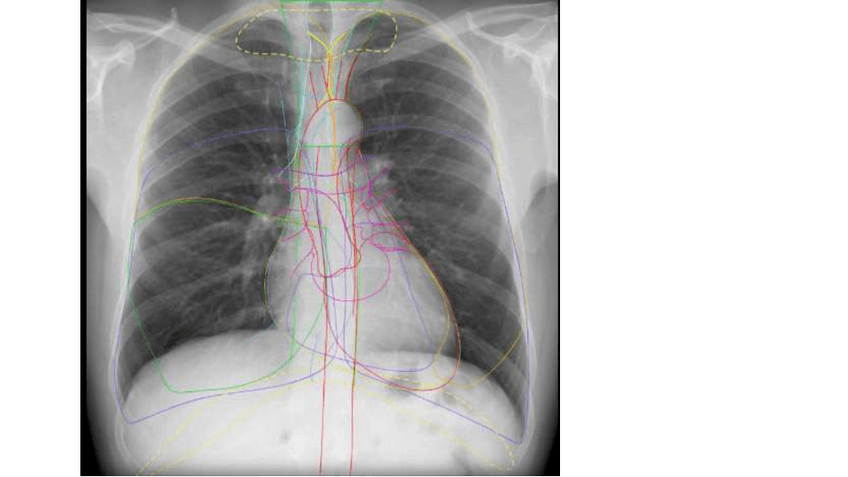

RADIOGRAFIA-DE-TORAX.pdf